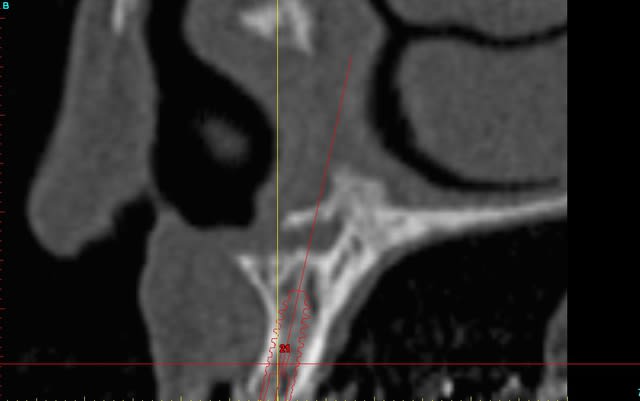

le scan n'est pas terrible, mais suffisant pour voir que 22 une fois extraite, ne va pas etre simple à implanter, par contre 11/21 avec un peu d'expansion...

Des lecross section21 jinha0 - Eugenol

Des lecross section sf6tbl - Eugenol

Des le cross section 12 vyz5ug - Eugenol

Des le cross section 22 w31w6b - Eugenol